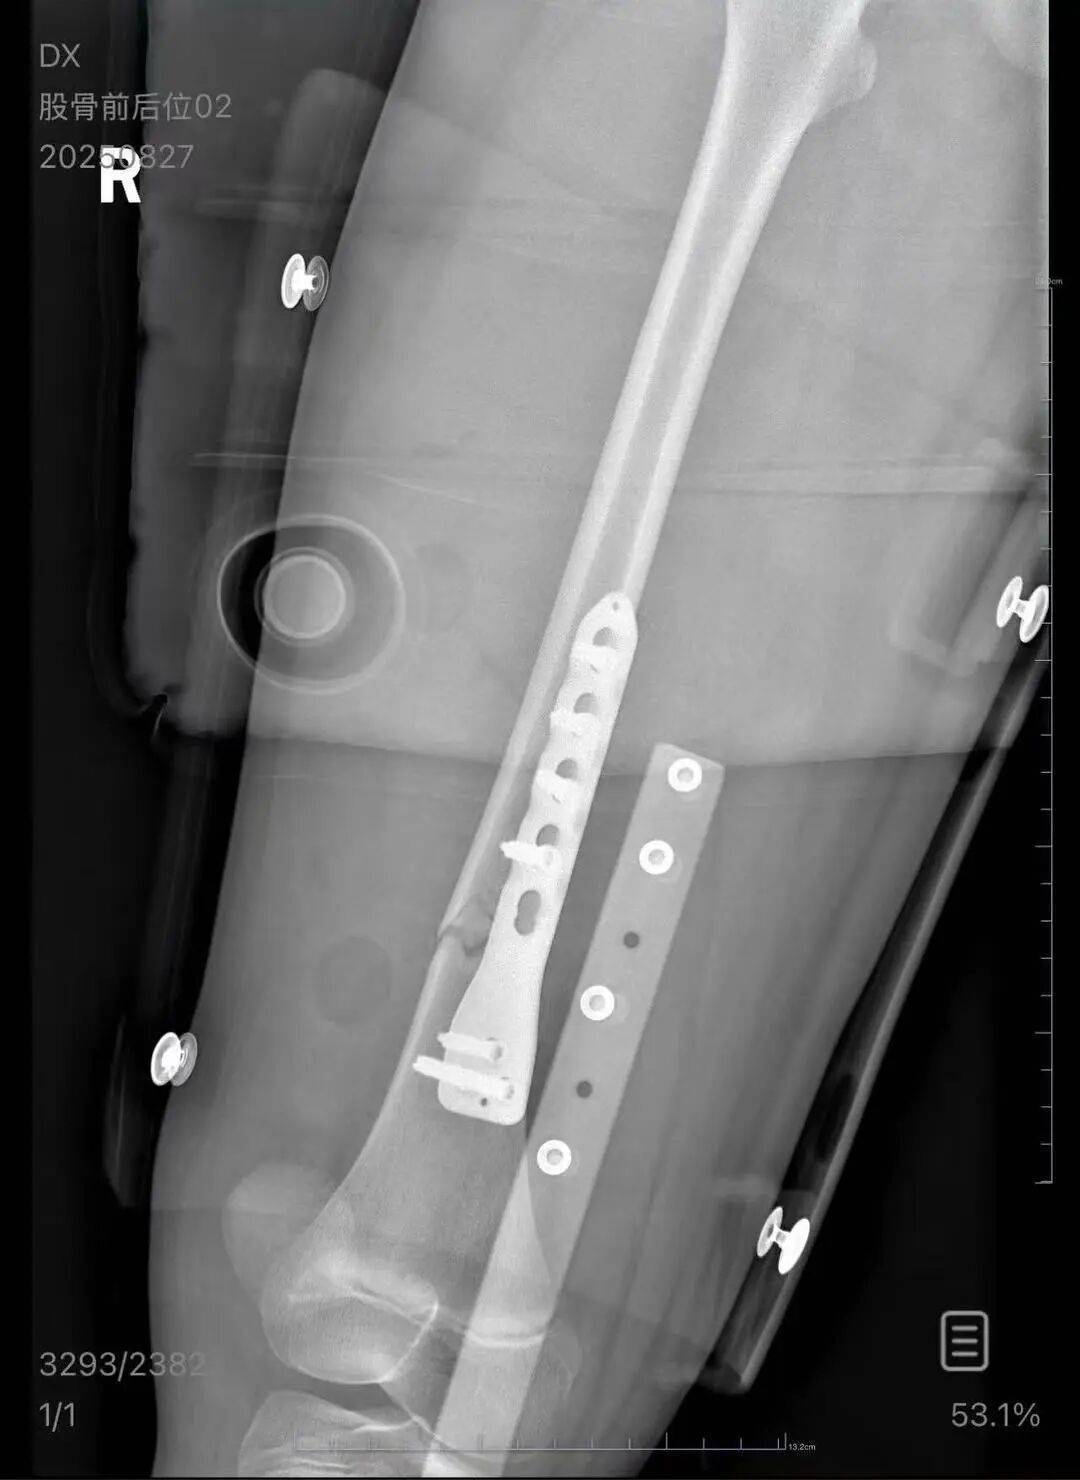

▲朱女士女儿手术后拍的X光片 受访者供图

朱女士向记者出示的医院病历显示,8月24日凌晨,朱女士的女儿到医院就诊酒鬼酒股票。医院诊断朱女士的女儿右股骨骨折,需要住院进一步治疗。

朱女士称,自己是离异状态,为了照顾小孩请假在家,也没有经济来源酒鬼酒股票。“现在孩子的医药费用已经花了5万多,后期还要进行康复治疗,我的压力非常大。”“医生说孩子还小,恢复快,钢板固定后很难恢复如初,甚至可能会出现长短腿的现象。”